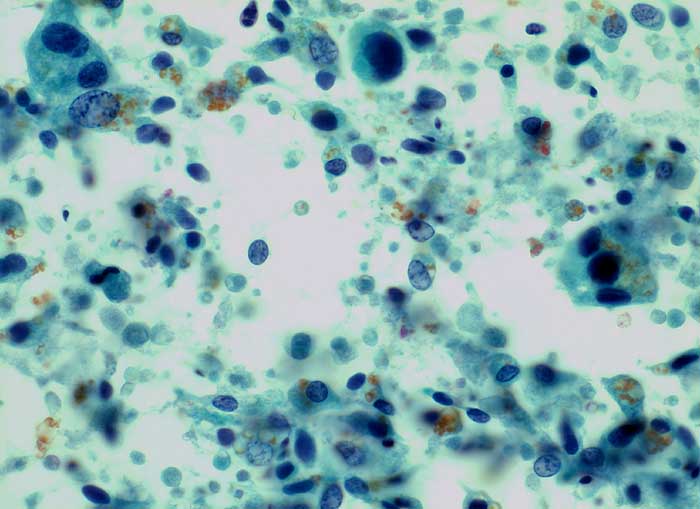

Samenblasenepithelien

Samenblase, Spülzytologie: Ausgeprägte Pleomorphie. Vergrösserte Kerne mit vergröbertem Chromatin und intranukleären Vakuolen. Pyknotische Kerne. Polygonale und spindelige Zellen. Reichlich goldgelbe Lipofuszinkörner.

Bei einer Prostatamassage können Samenblasenepithelien in den Urin gelagen, welche wegen ihrer ausgeprägten Pleomorphie zu einer Karzinomfehldiagnose verleiten können. Das Lipofuszinpigment hilft auf die richtige Spur.